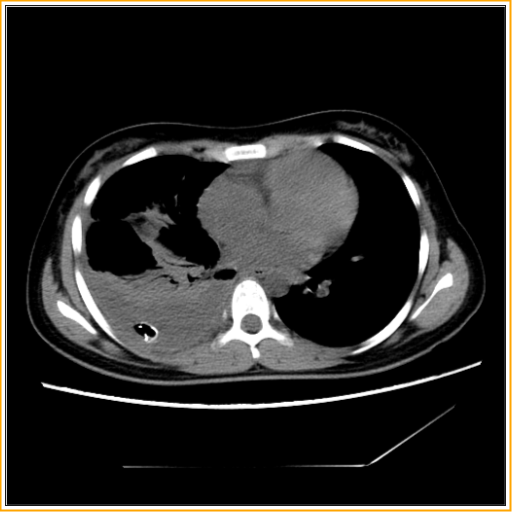

The patient is intubated with a double lumen tube for lung isolation and then placed in the lateral decubitus position, as for a thoracotomy. The chest tube which failed to remove the loculated collection or re-expand the lung is removed (Figure 1).

Figure 1: Loculated collection with collapsed lung and chest drain.